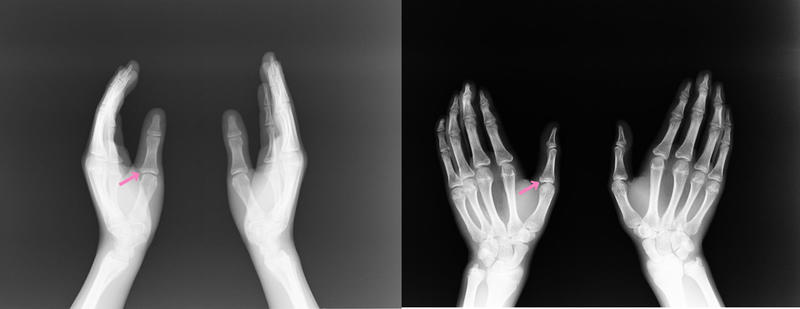

トレーニング中、バービージャンプをしようと、

手を突いた時に、左親指を突き損ね負傷。

やはり骨折・・・親指の基節骨の付け根が折れていました。